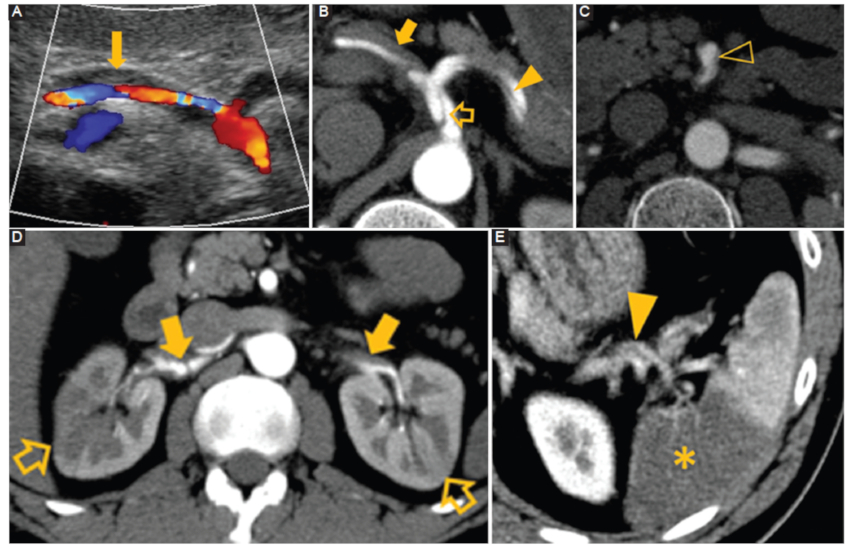

Enfermedad vascular no aterosclerótica y no inflamatoria de origen desconocido que afecta a las arterias viscerales del abdomen. Fisiopatológicamente comienza con una mediólisis, que implica la vacuolización y lisis de las células del músculo liso externo en la capa media. A continuación, un desgarro que separa el músculo medial externo de la adventicia ocurre con pérdida transmural parcheada de la lámina elástica externa. Cuando se completa la mediólisis, la lámina elástica interna y la íntima eventualmente se destruyen, dando lugar a la formación de brechas arteriales. Estas brechas son áreas de debilidad, donde el lumen que contiene la sangre se encuentra en contacto con la capa adventicia. La sangre dentro de la brecha puede disecar a través de una rotura hacia la media y formar hematomas intramurales y aneurismas disecantes11. En ecografía y TC se pueden apreciar múltiples zonas de estenosis, disecciones y trombos en arterias abdominales (Fig. 7) (12.

Figura 7

Mediólisis arterial segmentaria. Hombre de 38 años con pancreatitis aguda. A: la ecografía muestra un diámetro aumentado de la arteria hepática común y esplénica con material ecogénico que ocupa parcialmente el lumen (flecha). B: TC con contraste corte axial. Se identifica una estenosis secundaria a un trombo en la arteria hepática (flecha) asociado a colgajos de disección en el tronco celíaco (flecha hueca) y la arteria esplénica (cabeza de flecha). C: TC con contraste corte axial. Disección de la arteria mesentérica superior (cabeza de flecha hueca). D: TC con contraste corte axial. Estenosis, disección y presencia de trombos en ambas arterias renales (flecha) asociado a defectos de perfusión (flechas huecas). E: TC con contraste corte axial. Disección de la arteria esplénica (punta de flecha) con un defecto de perfusión (asterisco).